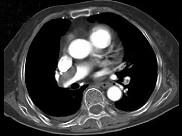

问题 82岁,女性,突发右侧胸痛,呼吸急促,行急诊CT检查,如图所示,请选择最佳答案 ( )

选项 A、肺动脉栓塞 B、肺动脉瘤 C、肺门淋巴结肿大 D、肺动静脉瘘 E、中央型肺癌

答案 A